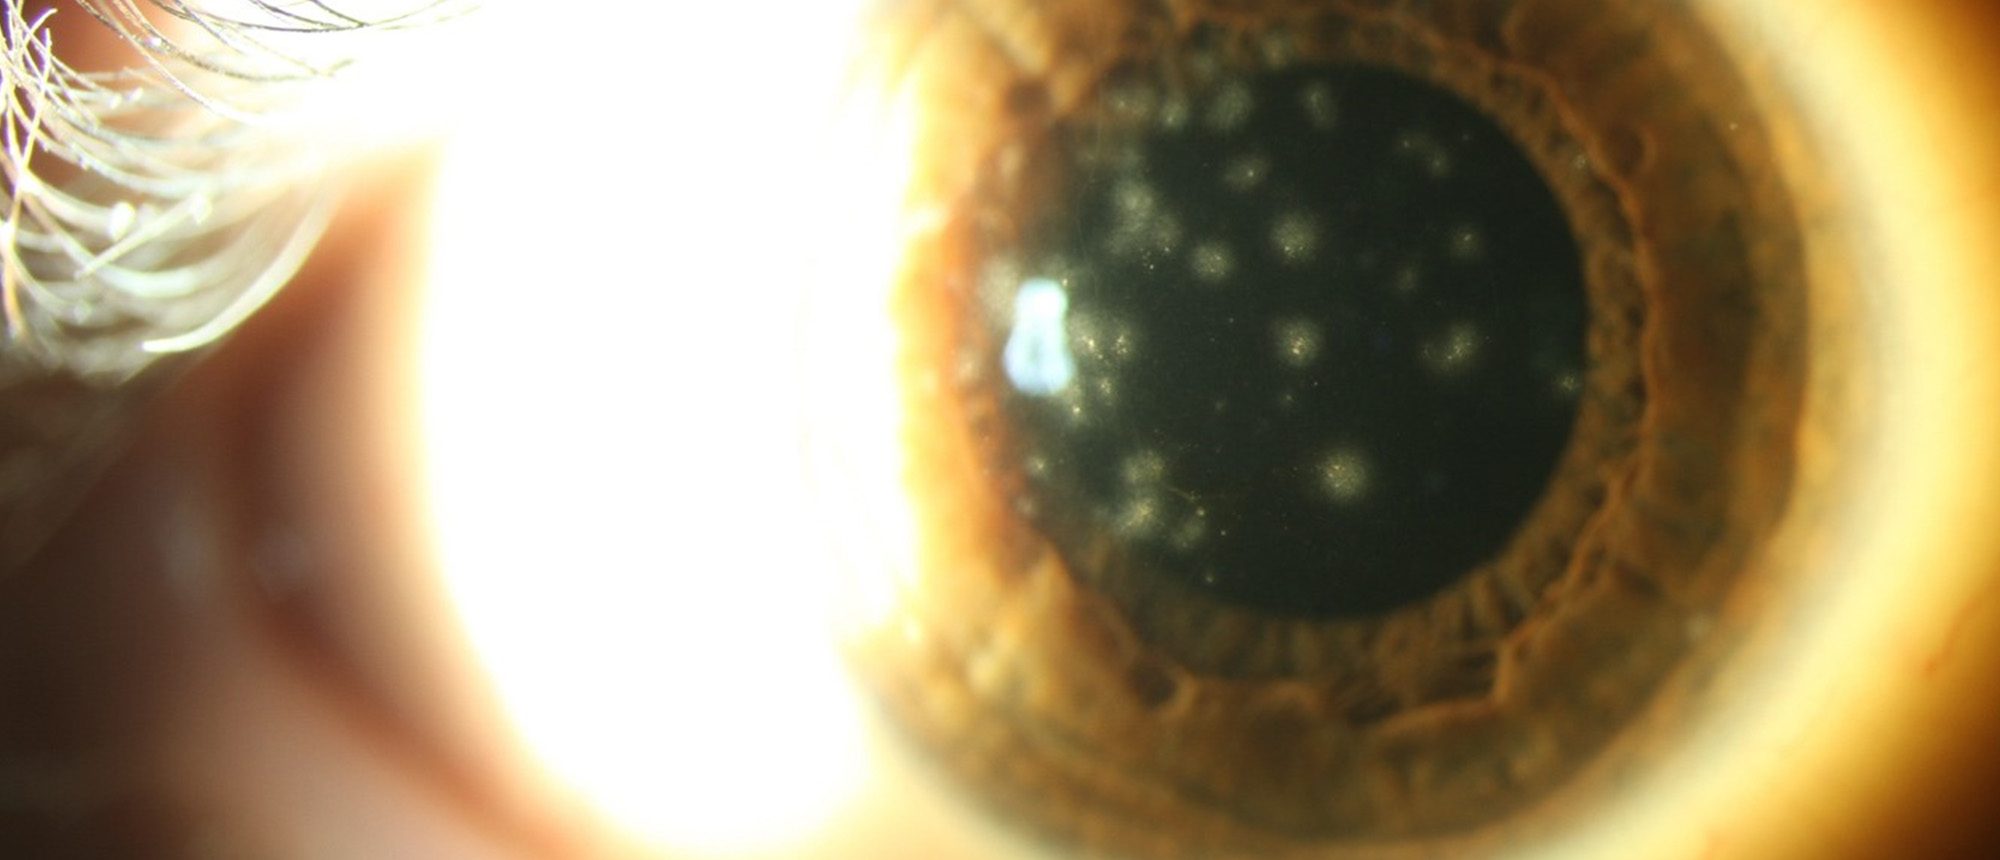

Abstract A healthy patient with prior history of LASIK OU presents with acute-onset decreased vision and eye pain in the left eye. On presentation, patient’s exam was notable for visual acuity of 20/20 in the right eye and 20/60 in the left eye. Intraocular pressure was 11 and 15 in the right and…

Post-LASIK Infectious Keratitis A healthy patient with prior history of LASIK OU presents with acute-onset decreased vision and eye pain in the left eye. On presentation, patient’s exam was notable for visual acuity of 20/20 in the right eye and 20/60 in the left eye. Intraocular pressure was 11 …